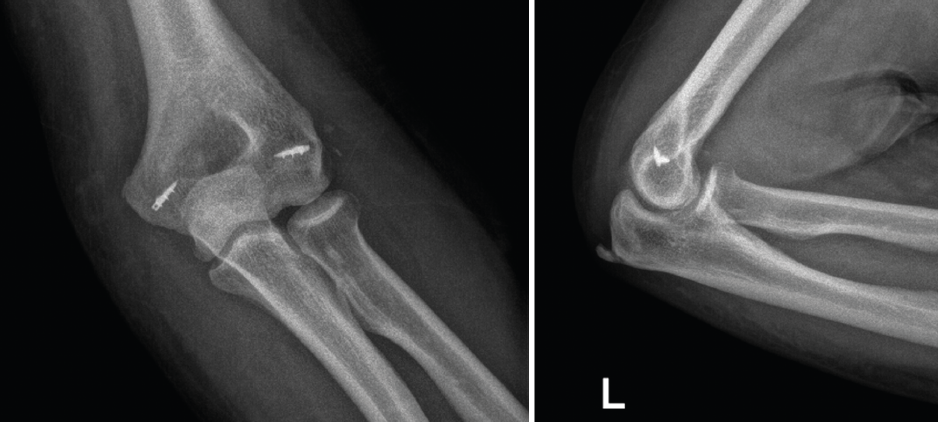

Figura 11. Radiografías de control en proyección anteroposterior y lateral en un paciente afecto de inestabilidad simple de codo persistente en el que se le realizó una reparación aguda del ligamento colateral lateral (LCL) y del ligamento colateral medial (LCM) mediante un sistema de arpones y suturas.

Típicamente, suele realizarse la reducción abierta mediante un abordaje posterior de codo o un abordaje lateral y medial combinado. En primer lugar, se aborda la zona lateral de la articulación del codo mediante un abordaje lateral de Kocher para realizar una inspección en busca de fragmentos óseos condrales o partes blandas interpuestas. El siguiente paso sería la reparación de LCL, el cual suele estar avulsionado de su inserción más proximal en el epicóndilo. La reparación típicamente se realiza mediante un sistema de anclaje con suturas, siendo importante también la posible lesión muscular de la región extensosupinadora. Una vez realizada la sutura de la zona ligamentosa y muscular lateral, se realiza una exploración bajo control escópico para evaluar la estabilidad del codo en rangos medios de movilidad y en posición de rotación neutra y pronación (evaluar la estabilidad del codo en supinación puede poner en riesgo la reparación del LCL). Si el codo sigue siendo inestable, entonces debe tenerse en cuenta realizar una reparación del LCM (Figura 10). Al igual que sucede con el LCL, la lesión del LCM suele localizarse en su inserción más proximal, aunque en ocasiones puede estar avulsionado del tubérculo sublime. La técnica de reparación empleada también suele ser mediante un sistema de arpón con suturas y, tras la realización de esta, deben repararse las lesiones asociadas en la musculatura flexopronadora (Figura 11). Si tras la reparación del LCL y del LCM, el codo sigue siendo inestable, debe colocarse un fijador externo de codo durante unas 4-6 semanas. Puede usarse, en función de las preferencias del cirujano, un fijador externo fijo o articulado.